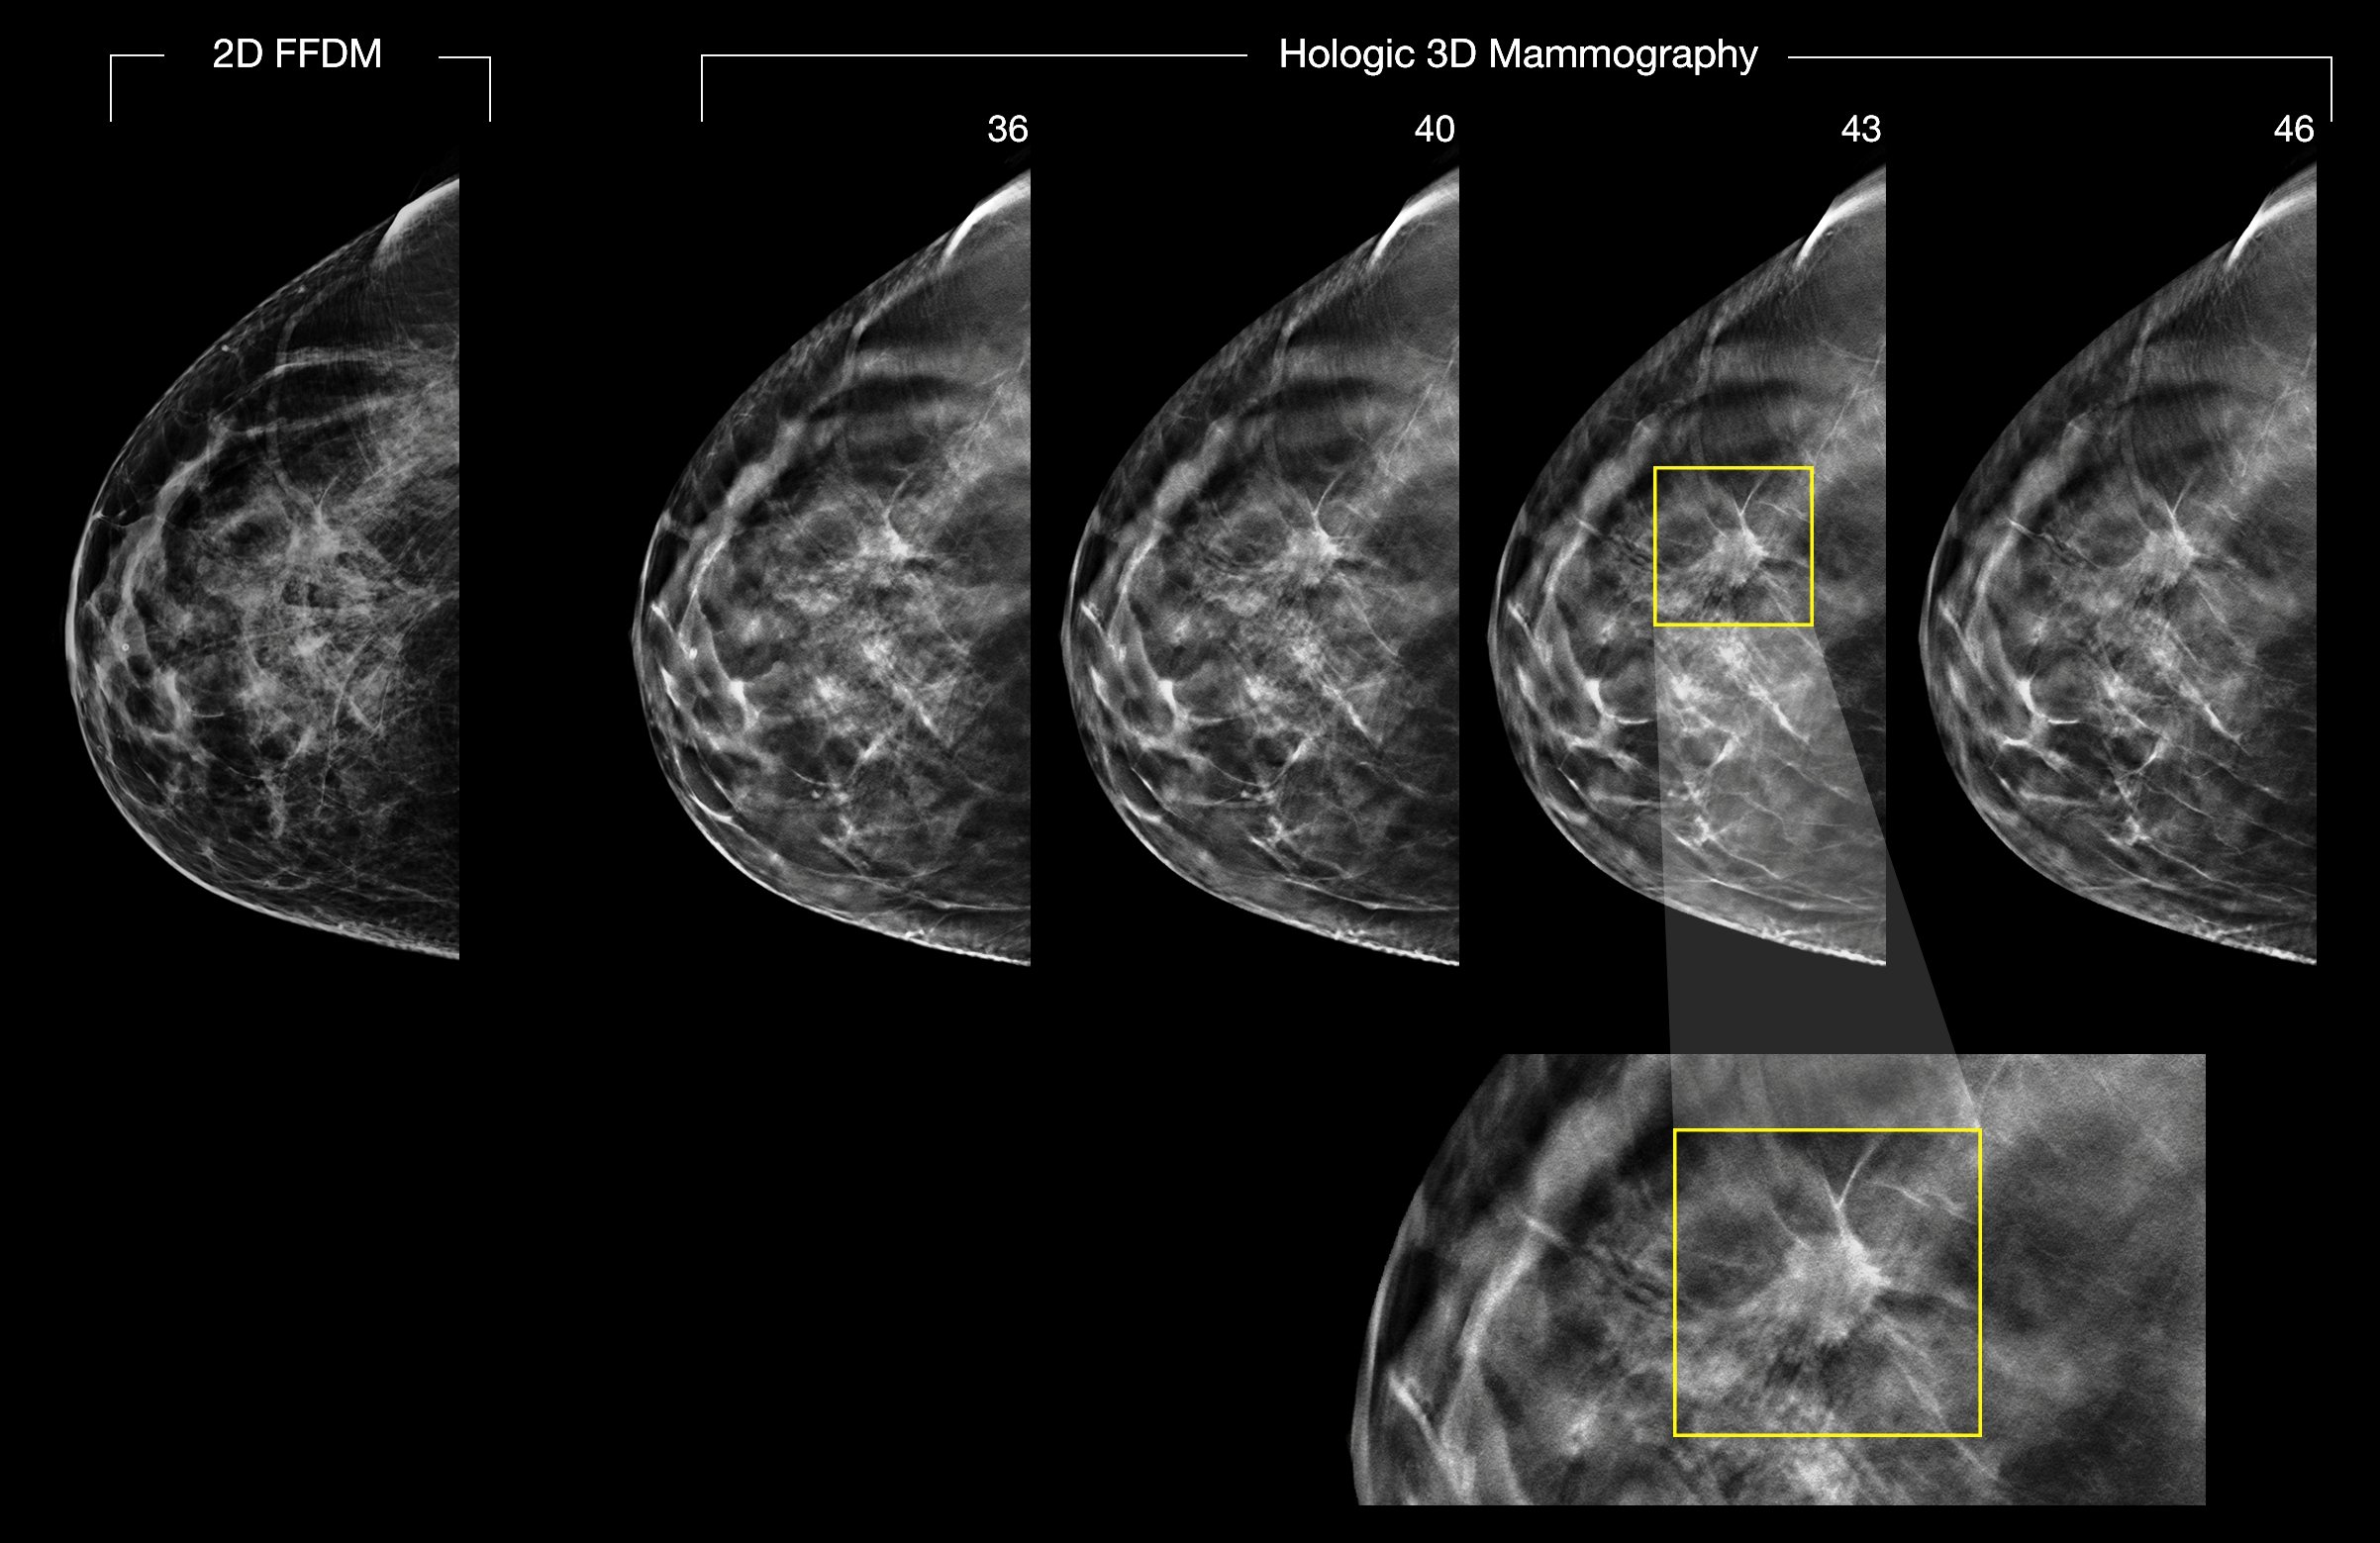

Since the widespread adoption of digital imaging and PACS, referring physicians seldom visit radiology reading rooms, substantially reducing a major source of feedback for radiologists. (Shown are 2-D and 3-D digital breast images.) A software module to be described April 5 at the SBI/ACR Breast Imaging Symposium has been providing that feedback for radiologists interpreting breast images at the University of Pittsburgh Medical Center. Image courtesy of Hologic